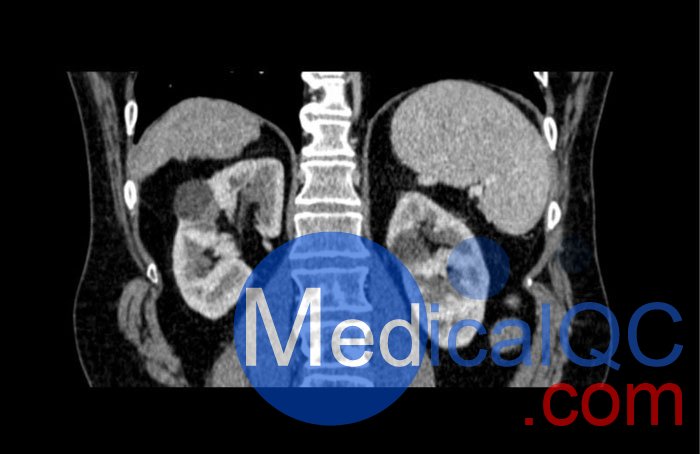

WEK53-04肝硬化腹部模體,WEK53-04門靜脈期腹部模體詳細(xì)介紹:

WEK53-04肝硬化腹部模體,WEK53-04腹部模體模擬了門靜脈期的造影劑增強(qiáng)腹部。它覆蓋了第十胸椎至第三腰椎。

WEK53-04肝硬化腹部模體,WEK53-04腹部模體代表膽囊切除術(shù)后的腹部,帶有小夾子。肝臟有肝硬化的典型體征,在第三腰椎水平植入下腔靜脈過濾器。兩個腎臟都有囊性病變,左側(cè)有一小塊腎結(jié)石。

該模型可用于 CT(包括 CBCT)以評估和優(yōu)化成像性能和后處理應(yīng)用,包括支持 AI 的應(yīng)用。它也適用于培訓(xùn)目的。

該模型提供了對軟組織和骨組織的詳細(xì)而逼真的模擬??障吨刑畛渲s-160HU的纖維素-聚合物復(fù)合材料。

WEK53-04肝硬化腹部模體,WEK53-04門靜脈期腹部模體診斷特征

真實(shí)模擬脈管系統(tǒng)、骨骼和軟組織,包括肝臟、胰腺、脾臟、腎上腺、腎臟、胃、小腸和結(jié)腸。

• 肝硬化

• 膽囊切除術(shù)

• 下腔靜脈濾器

• 腎囊腫

• 腎結(jié)石

• 淋巴結(jié)腫大

WEK53-04肝硬化腹部模體,WEK53-04門靜脈期腹部模體產(chǎn)品成像圖:

SAG: